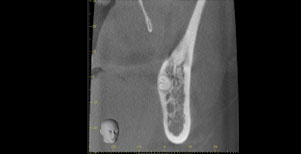

CT

CTで親知らずと神経(下歯槽管)の位置を確認しました。

親知らずと神経は一定の距離があり、麻痺などのリスクがほとんどないと判断できます。